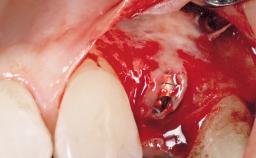

Immediate Placement of an Implant in a Maxillary Right Central Incisor Site

A 30-year-old female patient was referred to the office for the treatment of tooth 11. Her chief concern at the initial visit was to inquire, “Why is my tooth pink?” Upon clinical examination, it was determined that tooth 11 had a previous history of trauma and that the clinical crown had become noticeably pink in color as a result of internal resorption. This diagnosis was confirmed radiographically, indicating a large radiolucency involving the central and distal portions of the clinical crown. It was determined that restoration of this tooth was not possible, and that extraction was indicated. The presence of a mid-line diastema, which the patient wanted to reproduce, directed the treatment plan for tooth replacement utilizing a dental implant.

| Bone Augmentation | Horizontal|Simultaneous |

| Augmentation Materials | Autogenous chips|Membrane |